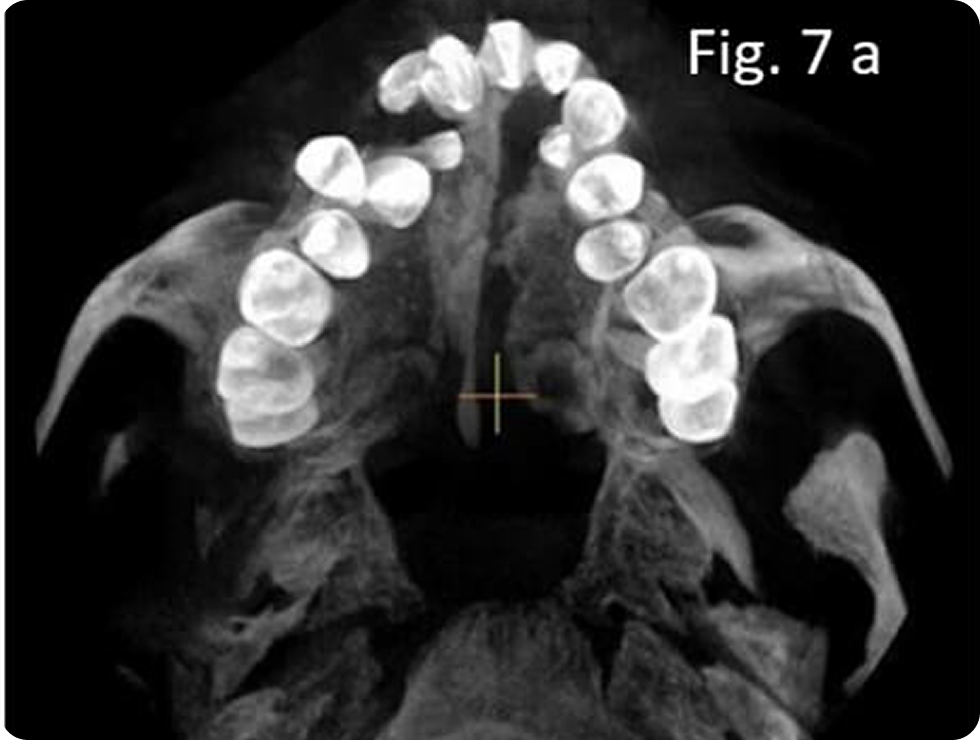

- Problemas dentales: El desarrollo dental puede verse afectado, con dientes que no se alinean correctamente o problemas en la erupción dental.

- Ortopedia: Muchas veces es necesario “orientar” o “estimular” los huesos de la cara mientras el paciente está en crecimiento.

- Ortodoncia: A medida que los dientes de los niños crecen, puede ser necesario el uso de aparatos ortodónticos para corregir problemas de alineación y mordida.

- Ortopedia: Para orientar, estimular o dirigir el crecimiento de los huesos de la cara.

- Ortodoncia: A medida que el niño crece, es probable que necesite aparatos ortodónticos para corregir problemas de alineación de los dientes y la mordida, ya que la fisura puede afectar el desarrollo dental.

- Tratamientos dentales: Algunos niños con paladar fisurado pueden tener dientes que no erupcionan correctamente o que están mal alineados debido a la fisura, lo que podría requerir restauraciones o intervenciones adicionales.